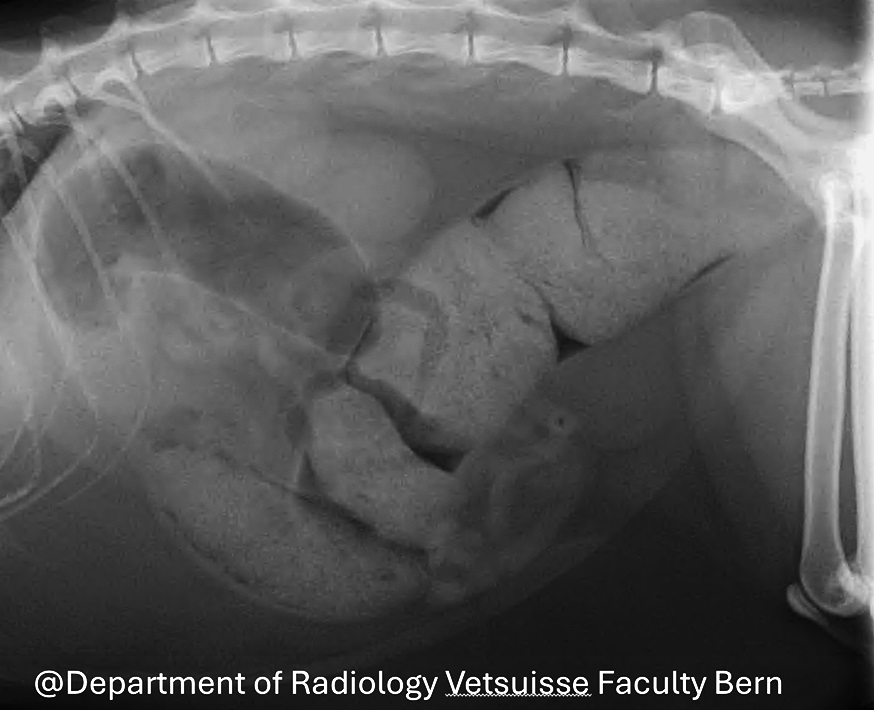

Das primäre diagnostische Mittel zur Beurteilung des Megakolons ist die Röntgenaufnahme.

Das Röntgenbild zeigt eine massive Dilatation des Dickdarms mit Ansammlung von stark verdichtetem Kot (Abb. 2).